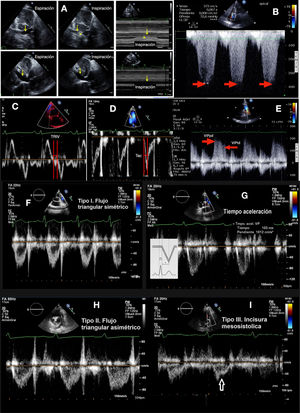

A. TAPSE; B. FAC; C. Doppler tisular. La flecha señala la onda sistólica y la estrella la velocidad de la onda e. D. Índice de TEI: mide el cociente entre los tiempos de contracción y relajación isovolumétricos en relación con la eyección sistólica. Se puede cuantificar con Doppler pulsado o a partir del registro de Doppler tisular. La ventaja del Doppler tisular es que permite recoger toda la información del ciclo cardíaco en el mismo latido y mejora la reproducibilidad de la técnica. Se medirá el tiempo de contracción isovolumétrica (ICT), el tiempo de relajación isovolumétrica (IRT) y el tiempo eyectivo (ET) en el espectro del Doppler tisular pulsado del anillo tricúspide lateral. E. Strain.

TAPSE (Excursión Sistólica del Plano del Anillo Triscuspídeo). Representa una medida de la función longitudinal. Se mide en el plano apical 4C con el cursor alineado de manera óptima en el anillo lateral tricuspídeo. Mide el grado de desplazamiento longitudinal del segmento anular de VD desde telediástole hasta el pico sistólico. Poco dependiente de buena calidad de imagen. Tiene valor pronóstico en la HTP31, y un valor <17mm sugiere disfunción sistólica del VD24. Presenta limitaciones en pacientes postoperados de cirugía cardíaca (fig. 3A).

FAC (Cambio del Área Fraccional). Es una estimación de función global ventricular. Se cuantifica en el plano apical de 4C mediante un trazado del área de VD telediastólica (ATD) y telesistólica (ATS), se debe tener cuidado de incluir las trabéculas en la cavidad. Fórmula: (ATD-ATS)/ATD×100, valores <35% indican disfunción sistólica24. Es predictor independiente de insuficiencia cardíaca, muerte súbita, ictus y mortalidad en pacientes con TEP32. Comparado con el TAPSE, el FAC es más preciso para estimar la función sistólica tomando como referencia la RM33 (fig. 3B).

Tisular (DTI). Velocidad de la onda sistólica (Ś). Se obtiene en el plano apical de 4C mediante DTI, colocando el cursor del Doppler pulsado (PW) en la porción media del segmento basal del anillo lateral tricuspídeo. Mide la velocidad longitudinal. Aunque disminuye con la edad, un valor <9,5cm/s se considera anormal24 (fig. 3C).

Índice de Función Miocárdica del VD (RIMP) o índice de Tei. Es un índice del rendimiento global del VD. Los intervalos de tiempo de contracción isovolumétrica (TCIV), tiempo de relajación isovolumétrica (TRIV) y tiempo de eyección (TE) deben medirse a partir del mismo latido cardíaco utilizando PW o DTI en el anillo lateral tricuspídeo. Es importante asegurarse de que latidos no consecutivos tengan intervalos RR similares. Puede estar infraestimado en condiciones de presiones elevadas de AD, lo que acortará el TRIV. RIMP>0,43 por PW y >0,54 por DTI indican disfunción del VD24 (fig. 3D).

Imagen de deformación tisular strain/strain rate. Los datos derivados del estudio con DTI se pueden utilizar para determinar el grado de deformación miocárdica de la pared libre (strain) y la velocidad de deformación miocárdica (strain rate). El strain y el strain rate estiman la función sistólica global y regional del VD, respectivamente. El strain se define como el porcentaje de acortamiento sistólico de la pared libre del VD desde la base hasta el ápex, mientras que el strain rate es la velocidad de este acortamiento24. Ambos tienen buena correlación con la contractilidad miocárdica34, sin embargo, el strain está menos influido por el movimiento del corazón, por lo que se considera un parámetro más fiable, aunque es dependiente de las condiciones de carga. El strain debe medirse desde la ventana apical de 4C sin angulación, con una imagen de gran calidad ya que la reverberación y artefactos pueden afectar en la colocación de los puntos de referencia, e infraestimar su cuantificación. Los puntos de referencia se deben limitar a la pared libre miocárdica excluyendo pericardio, lo que puede resultar difícil dado que la pared libre del VD suele ser delgada. Se considera normal un valor >–20%24 (fig. 3E).